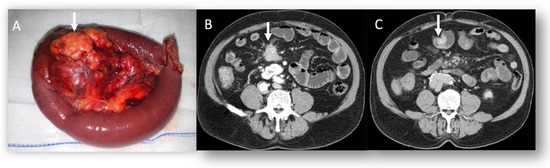

3.1. Pancreatic NENs

- Ciaravino, V.; De Robertis, R.; Martini, P.T.; Cardobi, N.; Cingarlini, S.; Amodio, A.; Landoni, L.; Capelli, P.; D’Onofrio, M. Imaging presentation of pancreatic neuroendocrine neoplasms. Insights Imag. 2018, 9, 943. [Google Scholar] [CrossRef] [PubMed]